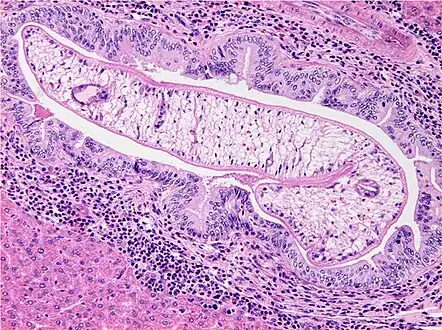

Photomicrograph of an adult O. viverrini in bile ducts of experimentally infected hamster

Generally, opisthorchiasis due to O. viverrini is harmless without any clinical symptoms. Mild symptoms may appear such as dyspepsia, abdominal pain, constipation, or diarrhoea. However, under severe infection, enlargement of liver (hepatomegaly) and malnutrition are observed. In rare cases, cholangitis, cholecystitis, and cholangiocarcinoma can also develop. In humans,O. viverrini inhabits mainly the bile ducts, and rarely, the gall bladder and pancreatic duct. Heavy infection can produce problems in the liver, gall bladder, and bile ducts. The bile ducts of heavily infected patients are usually dilated and indicate fibrosis.[24][25] Pathological effects on the bile ducts include inflammation, epithelial desquamation, goblet-cell metaplasia, epithelial and adenomatous hyperplasia, and periductal fibrosis.[26] The collective effects in addition to specific parasite secretion and the host's immune reactions account for the development of cholangiocarcinoma. The infection is not immediately life-threatening; cancer develops after 30–40 years, but death occurs very fast, within 3–6 months of diagnosis.[17]